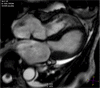

Takotsubo cardiomyopathy

Keywords: Apical ballooning syndrome; broken heart syndrome; cardiomyopathies; female; magnetic resonance imaging; sex factors; stress cardiomyopathy; takotsubo cardiomyopathy/diagnosis/drug therapy/epidemiology/etiology/physiology/physiopathology/psychology/surgery/therapy; ventricular dysfunction, left.